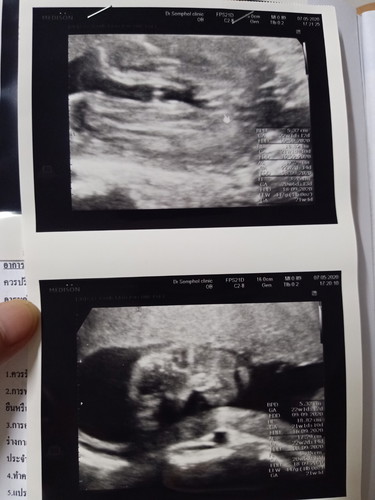

ใครดูเป็นดูให้หน่อยจ้า ญ หรือ ช.จ๊ะ

ใครดูเป็นช่วยดูให้หน่อยจ้า ญ หรือ ช.คะ...

น่าจะผู้หญิงค่ะ ภาพซาวด์ช้อนจากก้นน้องเห็นเป็นกลีบค่ะ

เห็นกลีบค่ะแม่ ผู้หญิงนะคะ

ผู้หญิงรึเปล่าคะแม่

เหมือนจะผุ้หญิงนะคะ

น้องดิ้นตอนซาวด์ด้วยคะภาพเลยไม่ค่อยชัด😅😅

ผู้หญิงแนร่เลยค่ะ

น่าจะหญิงนะคะ

คิดว่าผญ.นะคะ

น่าจะผญ.จ้า